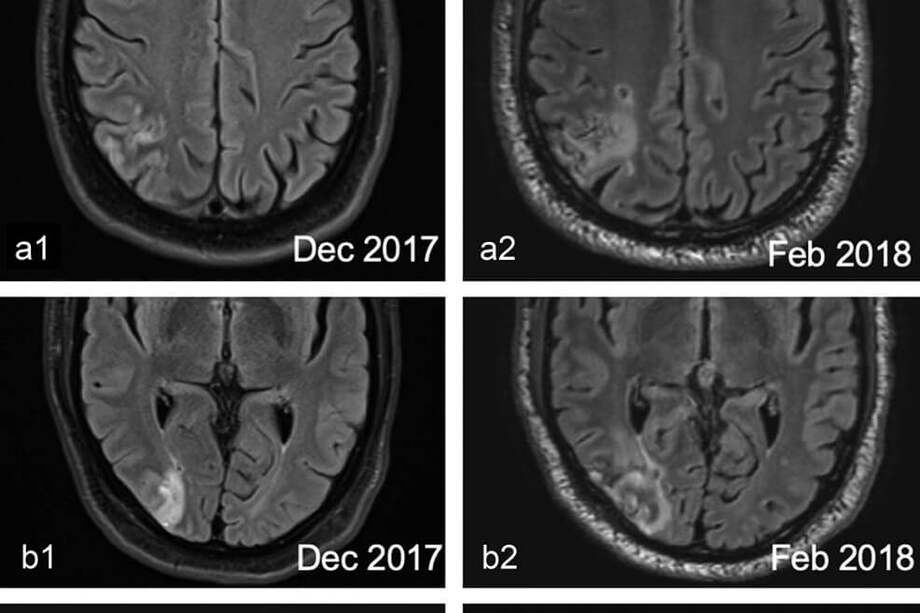

Los síntomas habían aparecido justo después del 28 de diciembre de 2017. Ese día había ingresado al hospital luego de presentar dolores en su brazo izquierdo. Días antes había tenido dificultades con su visión. El parte médico fue preciso: había sufrido un infarto en el lóbulo occipital y parietal derecho.

Luego de examinarlo nuevamente y hacerle una serie de pruebas computarizadas que evaluaban sus respuestas a estímulos visuales, los especialistas concluyeron que había sufrido daños en la parte del cerebro que se encarga del procesamiento visual. Y en un intento por reparar el daño causado, el sistema visual, extrañamente, creó ese efecto. El paciente siempre creyó que los objetos a su lado izquierdo eran más pequeños que los que estaban a su lado derecho.

En términos técnicos, apuntaron los médicos, el “infarto en nuestro paciente ha causado deficiencias sensoriales visuales contralesiones, por lo que un proceso inconsciente de orden superior intenta compensar el precio de crear un mundo ‘encogido’”.